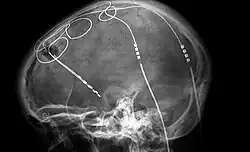

The efficacy of neuropsychiatric treatment has been questioned. This is particularly in regard to psychiatric drugs, of which the success of and mechanism of treatment is mixed and largely unknown respectively,[43] and the use of current neuroimaging technology for diagnostic and treatment purposes, which according to neuropsychiatrist Helen S. Mayberg is "without medical or scientific support,”[44] as results do not clarify causality.[45]